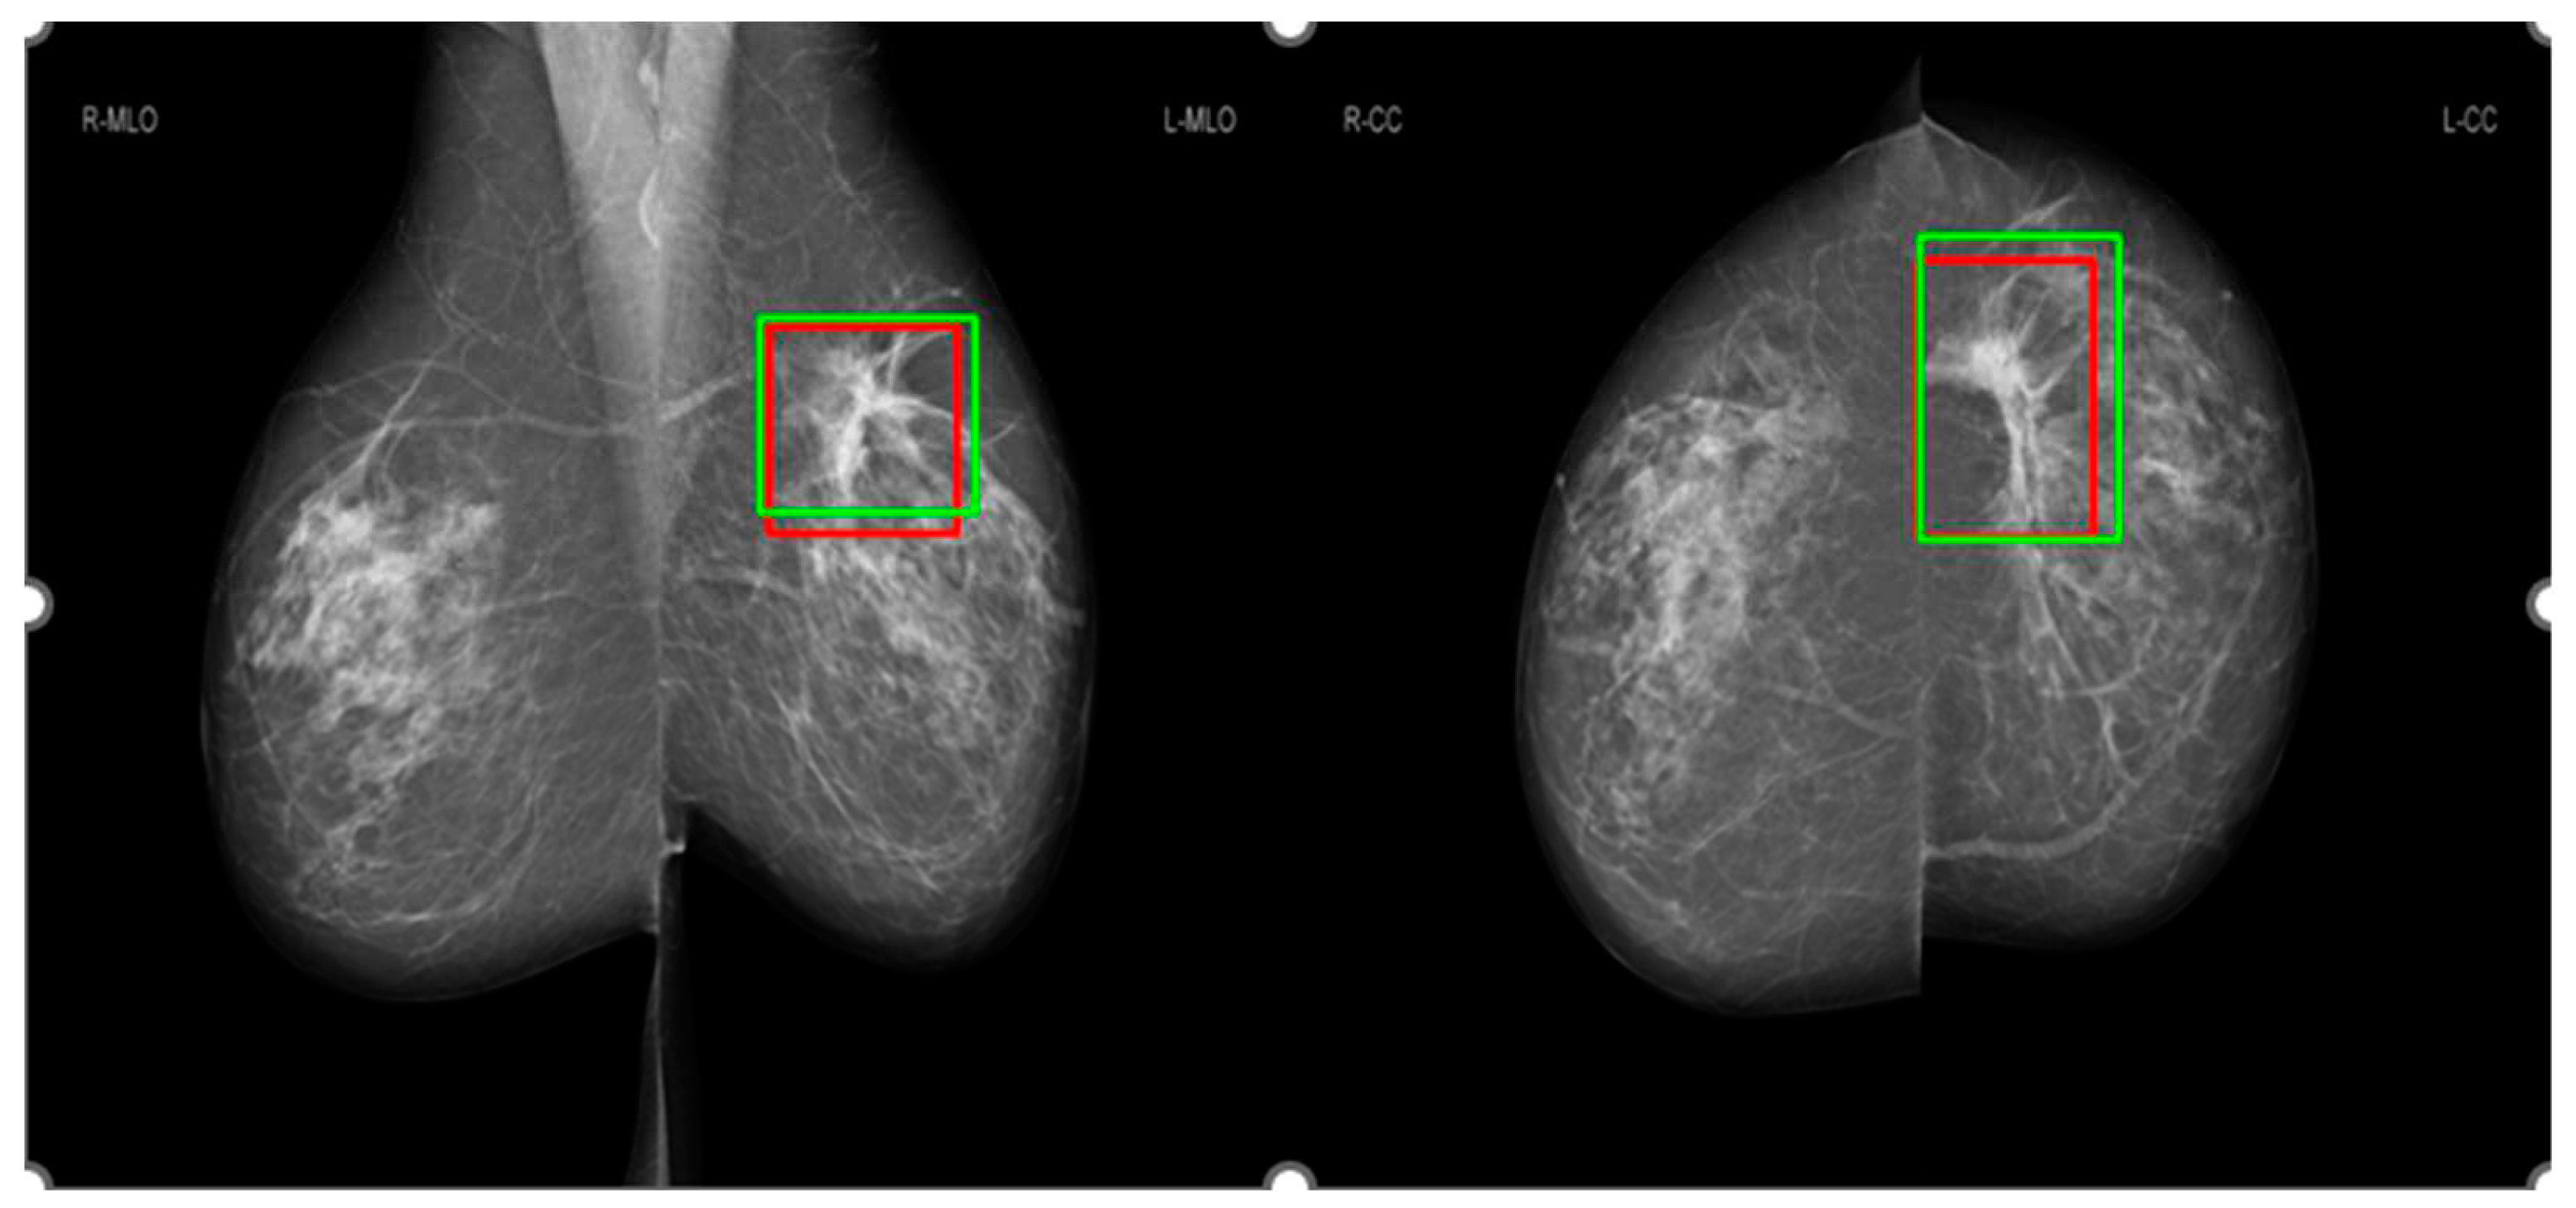

3.3. Comparison of salience maps on original and locally-enhanced mammographic images